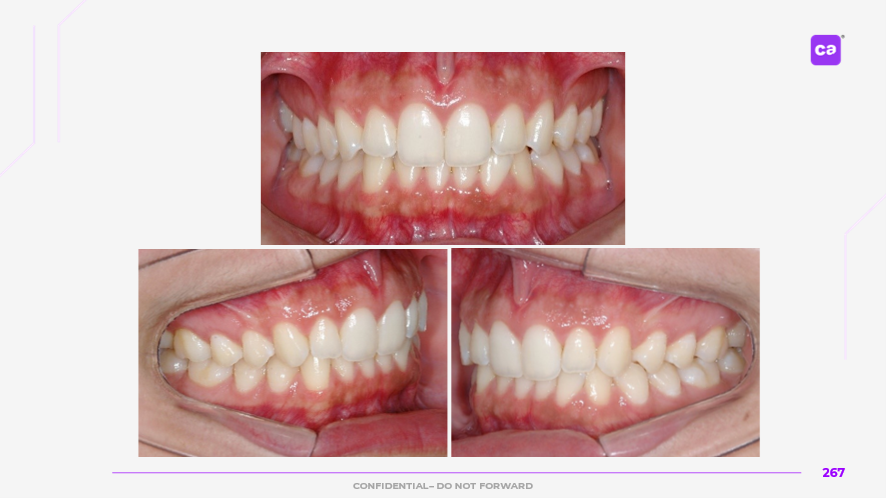

Figuras 4 – Fotos intraorais do caso clínico apresentadas em norma oclusal superior e inferior:

a) Condição inicial do caso clínico

b) Condição final do caso clínico

Na sequência apresentada, com os registros e comparação das fotos intraorais, observa-se a evolução do caso clínico desde a condição inicial até a finalização do tratamento com a conclusão do uso da série de alinhadores. Os resultados evidenciam a previsibilidade e acurácia do tratamento real em comparação às simulações e ao planejamento virtual inicial.

Observa-se a correção da sobremordida (mordida profunda), com avanço e torque vestibular dos incisivos superiores, juntamente com o nivelamento e alinhamento dentário das arcadas superior e inferior.

Além disso, nota-se o ajuste da linha média dentária superior, garantindo sua coincidência com a linha média inferior, bem como a otimização da curva e da estética do sorriso.